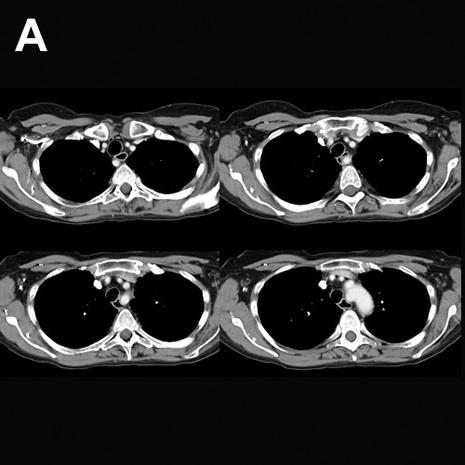

Image A shows an anomaly of the aortic branches:

Image B shows labels on the structures in these CT images.

The aorta is outlined in red.  The right subclavian artery has an anomalous origin, coming off as the last branch of the aortic arch and passing posterior to the trachea and esophagus.  This is called an aberrant right subclavian artery.  The aberrant vessel is shown in pink.  The right common carotid artery (there is no brachiocephalic artery in this case, since the right common carotid artery and right subclavian artery do not arise from a common trunnk) is shown in blue, the left common carotid artery in yellow and the left subclavian artery in green.